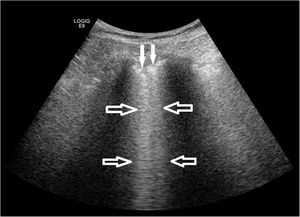

Fig. 2 shows the pathological processes in which the respondents that performed LUS applied the technique in their clinical practice. It was most frequently used to detect pleural effusion (50% of the respondents) and to guide thoracentesis or pleural biopsy (44.70% of respondents), while it was used substantially less in ILD (21.22% of the respondents). Accordingly, only 20 (14.93%) out of 134 answered yes to the question as to whether they performed LUS in ILD, for the following purposes: diagnosis (18; 13.64% of the respondents), therapeutic decision support (9; 6.82% of the respondents), monitoring of therapeutic response (7; 5.30% of the respondents), and research (13; 9.85% of the respondents). Most of the respondents who performed LUS in ILD were evaluating the presence of B-lines and pleural abnormalities as ultrasound markers of the disease process (Fig. 3).